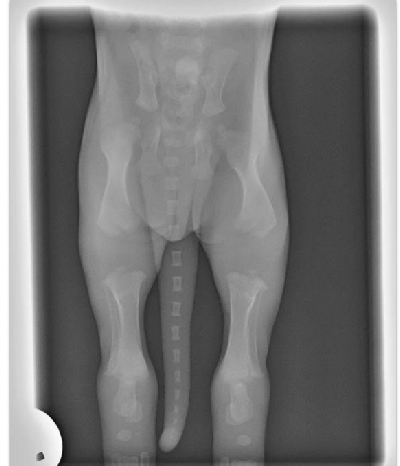

Below is an x-ray of a puppy at 2 weeks old. Just look to see how far the bones have to grow to just become proper bony joints that have correct feedback to the brain……this is why it is imperative that we don’t over exercise our puppies, and certainly not jump them or train them too hard before they are fully developed. This is a different age categories for different breeds, and if the dog has had any specific problems during its puppy hood. Please be careful at this stage so the dogs joints will last as well as they age! Longevity is the key.